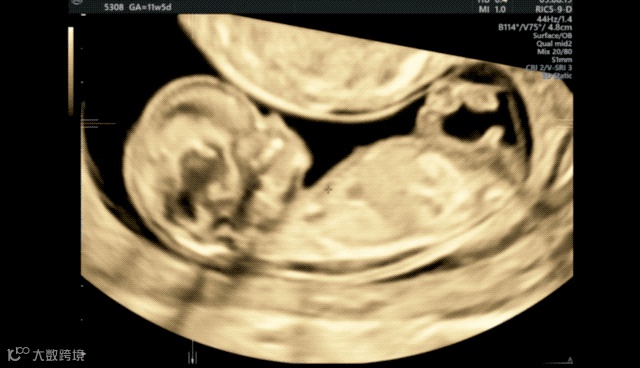

微调后,我们在菜单内选择a平面-单幅图像,放大,就可以测量头臀长。

接着继续放大a平面,使胎儿头胸部占据整个画面,微调后显示NT的两条线,降低增益,完成NT测量就可以了。